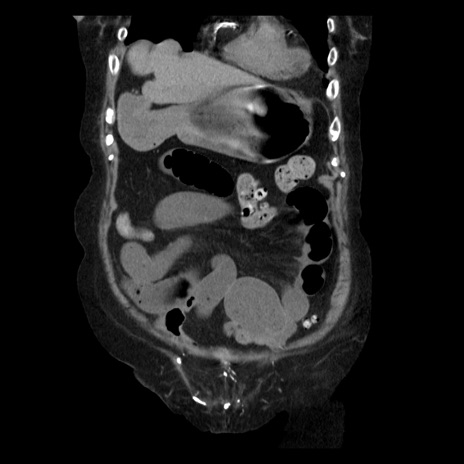

症例14(冠状断像)

【症例】 90歳代女性

【主訴】 腹痛・嘔吐

【現病歴】今朝から左側腹部痛を認めた。 経過観察していたが、嘔吐を認めたため来院。

【既往歴】 子宮癌術後

【身体所見】 意識清明、BP 127/54mmHg、P 98bpm Sp02 95%(RA)、BT 35.8°C、腹部平坦・軟腸ぜん動音聴取良好、右下腹部圧痛(+) 反跳痛なし

【データ】WBC 9800、CRP 0.46